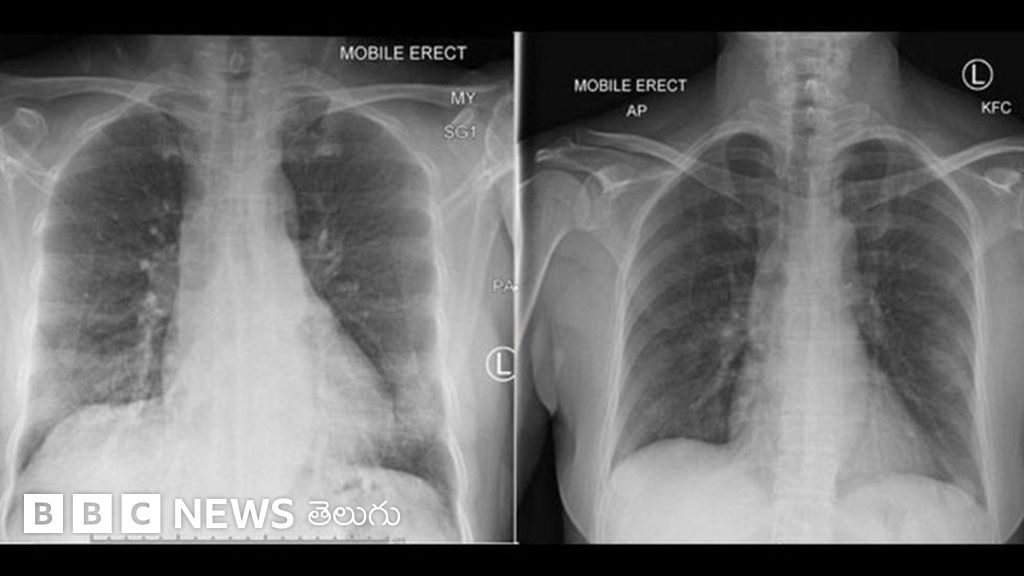

కోవిడ్-19 సోకిన వారిలో చాలా మంది కోలుకున్నారు. దీని అర్థం.. మన రోగనిరోధక వ్యవస్థ వైరస్తో విజయవంతంగా పోరాడగలదని మనకు ఇప్పటికే తెలుసు.

అయితే.. కోవిడ్-19తో పోరాడటానికి విడుదలైన నాలుగు రకాల రోగనిరోధక కణాలను శాస్త్రవేత్తలు మొదటిసారిగా గుర్తించారు.

ఈ వైరస్ సోకి ఒక మాదిరిగా అనారోగ్యానికి గురైన ఒక రోగిని అధ్యయనం చేసినపుడు ఈ కణాలను గమనించారు.

చైనాలోని ఉహాన్ నగరానికి చెందిన ఆ రోగి ఒక 47 సంవత్సరాల మహిళ. ఆమెకు గతంలో ఎటువంటి అనారోగ్య సమస్యలూ లేవు. ఆస్ట్రేలియాలోని ఒక ఆస్పత్రిలో చేరిన ఆమె 14 రోజుల్లో కోలుకున్నారు.

ఈ రోగిలో రోగనిరోధక వ్యవస్థ పూర్తి స్థాయి ప్రతిస్పందనను తమ బృందం పరీక్షించిందని ప్రొఫెసర్ కేథరీన్ బీబీసీకి చెప్పారు.

ఆ రోగి కోలుకోవటం మొదలవటానికి మూడు రోజుల ముందు.. ఆమె శరీరంలోని రక్తప్రవాహంలో నిర్దిష్ట కణాలను గుర్తించారు.